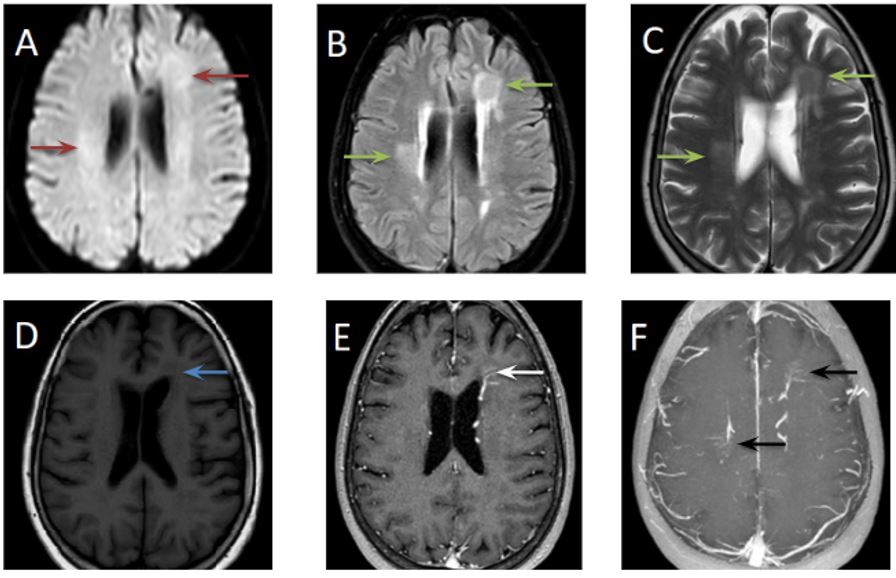

(A) Axial DWI. Se identifican lesiones no restrictivas (flechas rojas). Axial FLAIR (B) y T2 (C). Se observan dos imágenes de aspecto pseudonodular hiperintensas (flechas verdes) a nivel periventricular derecho y frontal izquierdo e hipointensas (flecha azul) T1 (D). Estas lesiones muestran realce al gadolinio de la vasculatura venosa que drena en la vena colectora, configurando el signo de la cabeza de Medusa (flecha blanca) (E) y RM axial MIP (flechas negras) (F).

Características diagnósticas clave: Rara vez se identifican en la TC sin contraste. La resonancia magnética ponderada en T1 y T2 sin contraste puede demostrar vacíos de flujo y artificios de cambio de fase producidos por la vena colectora. Se puede ver una señal T2/FLAIR alta en la sustancia blanca adyacente que simula una lesión pseudonodular. Con la administracion de gadolinio, el grupo de venas tiene una apariencia de rueda de radios, las venas son pequeñas en la periferia y se agrandan gradualmente a medida que se acercan a una vena de drenaje central. Esta apariencia se ha denominado caput medusae o cabeza de Medusa.